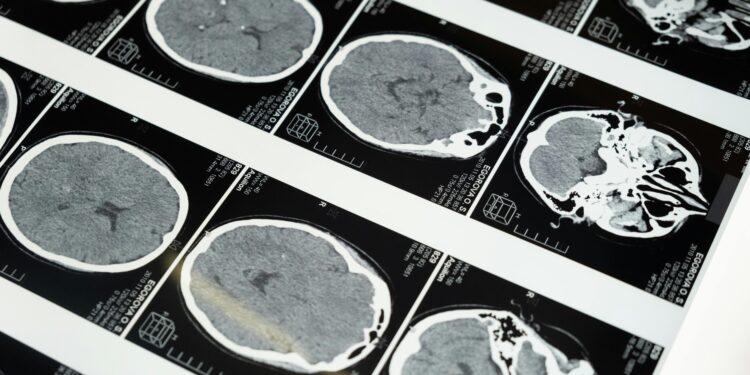

Descoberta recente da Universidade da Califórnia indica que pessoas com transtornos de ansiedade apresentam, em média, 8% menos colina no córtex pré-frontal.

Esse achado reflete a análise de 25 estudos anteriores, que reuniram dados de 712 participantes, dos quais 370 tinham diagnóstico de ansiedade. A redução desse nutriente, essencial para a função cerebral, pode abrir novas frentes no tratamento de distúrbios emocionais.

Níveis reduzidos de colina no cérebro, em particular no córtex pré-frontal, comprometem funções cognitivas essenciais. Essa ligação sugere que intervenções futuras podem aproveitar essa descoberta no desenvolvimento de tratamentos.